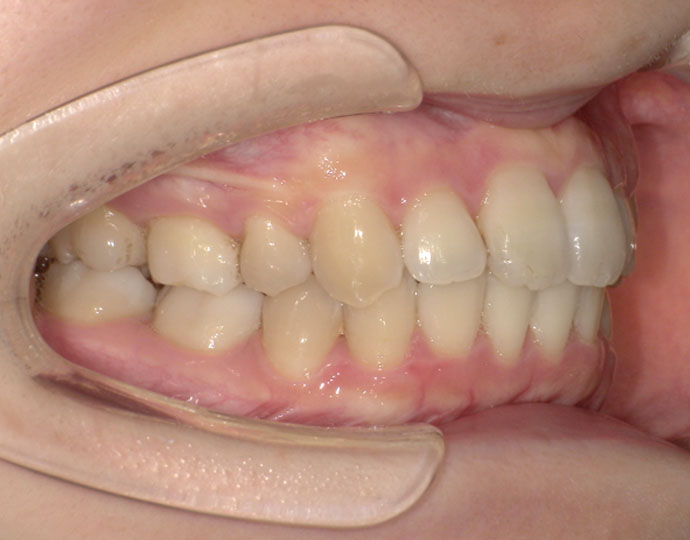

ワイヤー治療 叢生+上顎前突不正咬合 治療例

治療前

治療後

| 診断 | 叢生歯列を伴う上顎前突不正咬合 |

| 治療方針 | 上顎左右第一小臼歯、下顎左右第二小臼歯の抜歯 |

| 治療に使用した装置 | セルフライゲーションブラケット インプラントアンカースクリュー×2 |

| 治療期間 | 2年6カ月 |